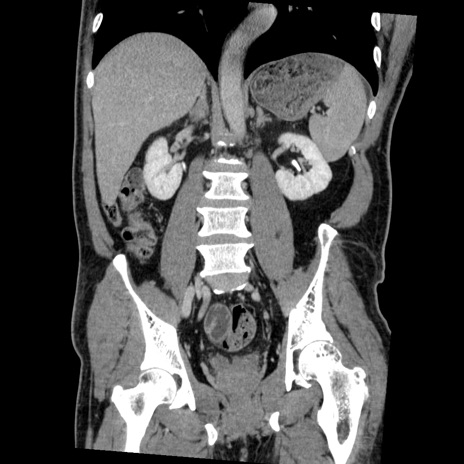

症例22(冠状断像)

【症例】50歳代男性

【主訴】腹痛

【現病歴】AVMからの被殻出血のため回復期リハ病棟入院中。 本日午後3時頃急に下腹部痛が出現した。

【既往歴】AVM、被殻出血、虫垂炎、高血圧

【身体所見】意識晴明、左半身不全麻痺、会話の理解は良好、36.5°C、腹部:膨隆、全体に板状硬、下腹部正中に圧痛点あり、反跳痛-、筋性防御不明、右下腹部にope scar

【データ】WBC 9400、CRP 0.06